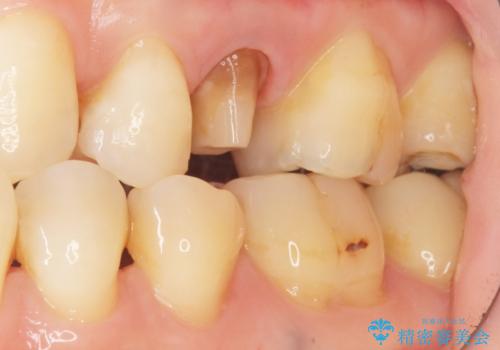

- 歯が欠けてしまったことを主訴に来院された患者様です。

欠けている奥歯(左上5)は失活歯で、保険内の銀の詰め物(メタルアンレー)で治療されていました。

金属の詰め物と土台を除去し、ファイバーコア(金属を使わない強くてしなやかな土台)を植立したのちセラミッククラウンによる補綴治療を行いました。

精査したところ、右上の奥歯(右上5)に根尖病変を認めたため、こちらは根管治療後にセラミッククラウンによる補綴を行いました。